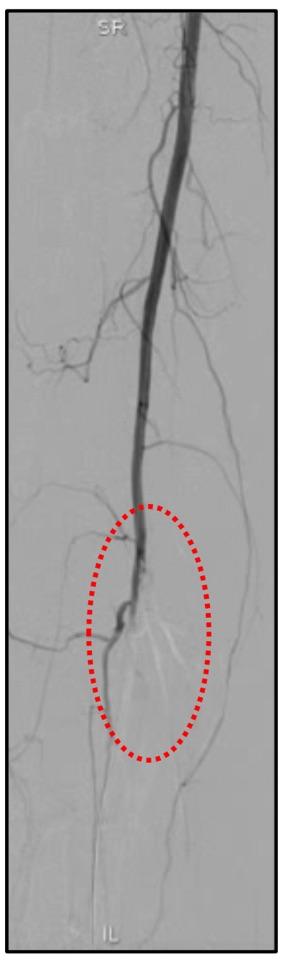

术后造影发现右小腿动脉血流中断,考虑栓子脱落引起

术中行吸栓及球囊扩张治疗